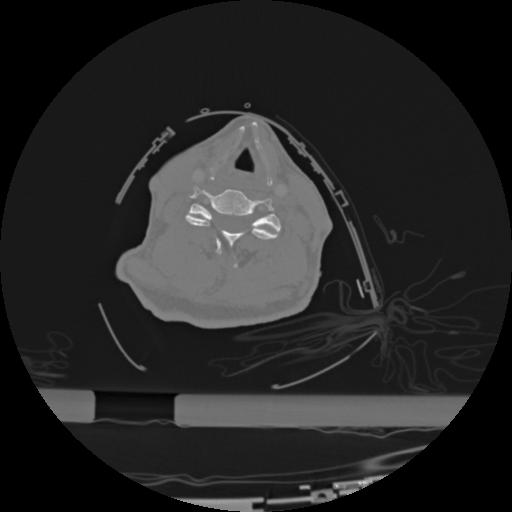

22 ANGIO,CE,Vol,0.5,ANGIO,,